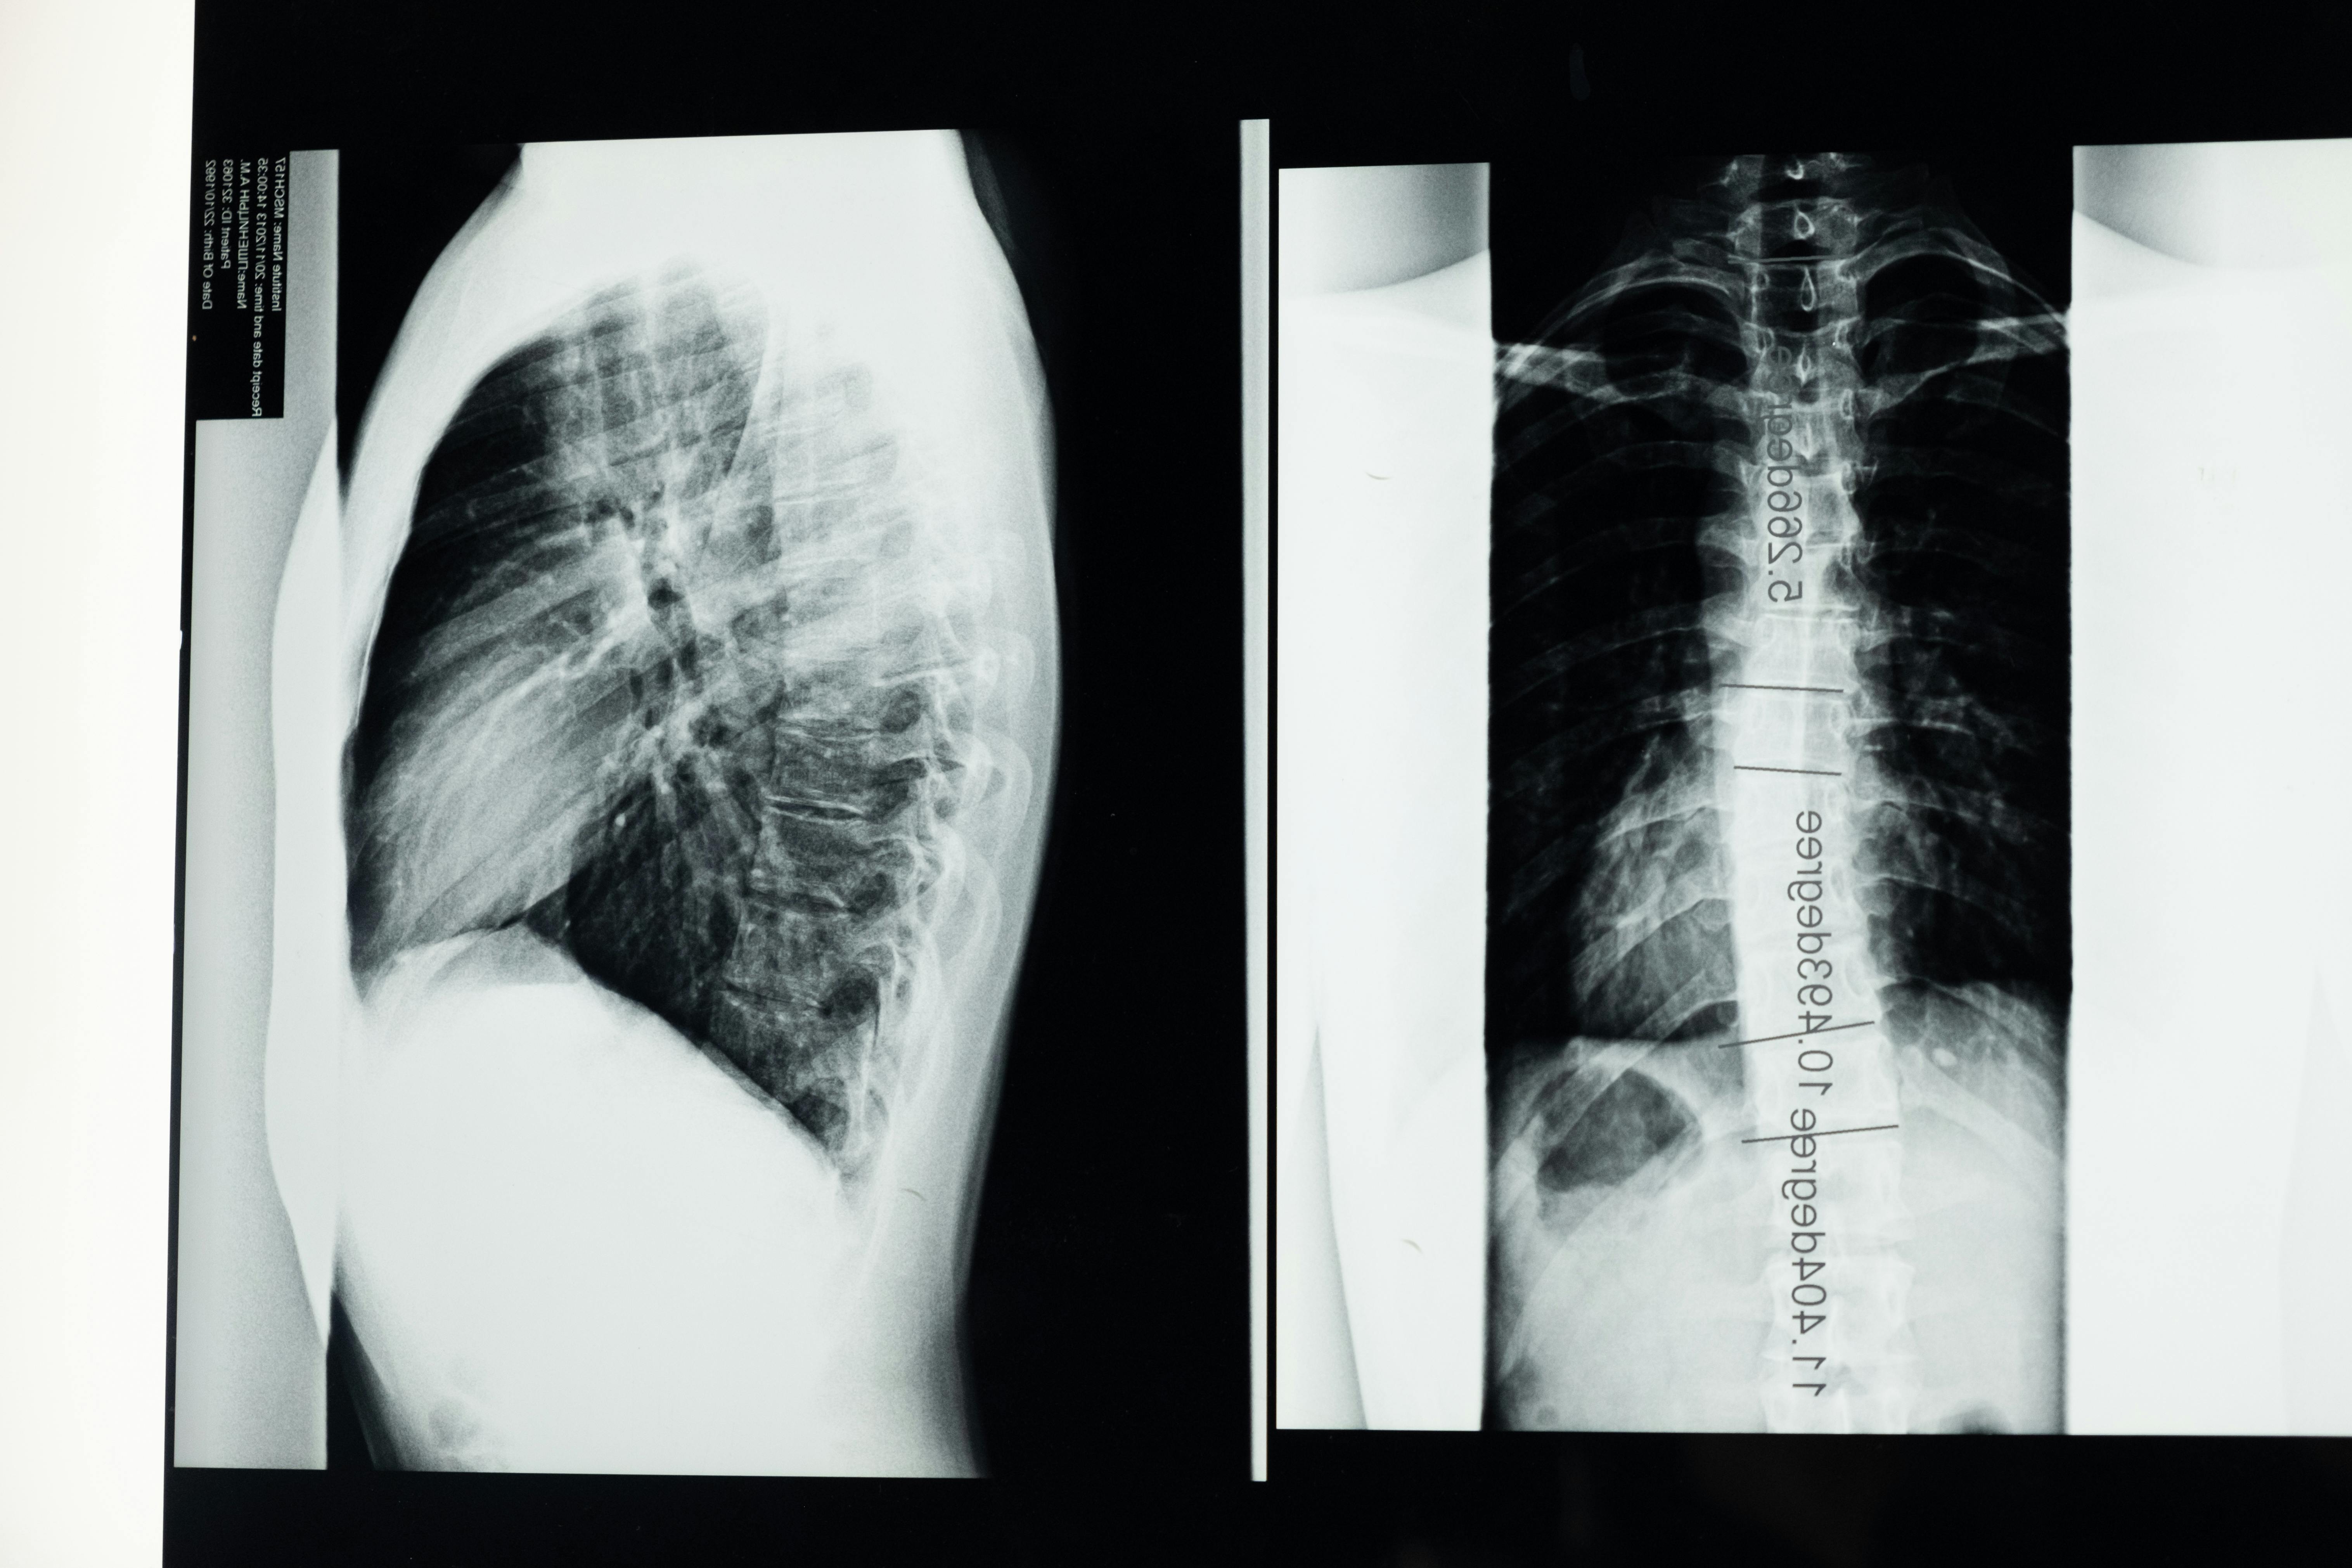

Spinal decompression therapy is a non-surgical, drug-free treatment designed to relieve pressure on the spine and support the body’s natural healing process. It is commonly used for disc injuries, sciatica, numbness and tingling in the arms or legs, and a range of other spine-related conditions that cause chronic pain or limited mobility. For many patients, spinal decompression offers a safe and effective alternative to surgery or long-term medication use.

At the Scoliosis Treatment Center with Dr. Collin Hilliard, DC, we focus on providing safe, non-surgical relief from spinal pain and nerve-related symptoms. Whether you’re dealing with a disc injury, sciatica, numbness and tingling in your arms or legs, or other conditions caused by pressure on spinal structures, spinal decompression therapy offers a gentle and effective path toward lasting comfort and function.

Dr. Hilliard is a 3rd-generation chiropractor and a CLEAR™ Certified Scoliosis Doctor, with decades of experience helping patients with complex spinal conditions. His work at Elite Chiropractic and the Scoliosis Treatment Center is grounded in a philosophy that the body can heal itself when pressure and nerve interference are reduced.